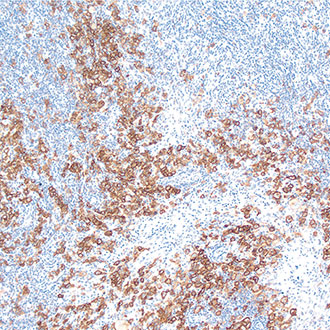

IHC

免疫组织化学(IHC)